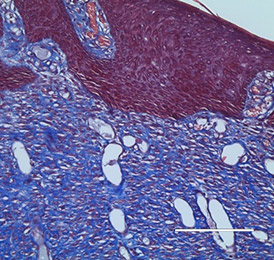

The bio-ConneKt® Wound Matrix is a collagen-based wound dressing for the local management of moderately to heavily exuding wounds. It is indicated for use wherever there is breach of the skin. Some of the common types of wounds where bio-ConneKt® Wound Matrix has been used include: full and partial thickness wounds, draining wounds, tunneling wounds, pressure sores/ulcers, venous ulcers, chronic vascular ulcers, diabetic ulcers, trauma wounds (e.g. abrasions, lacerations, partial thickness burns, skin tears), and surgical wounds (e.g. donor sites/grafts, post-laser surgery, post-Mohs’ surgery, podiatric wounds, dehisced surgical incisions).